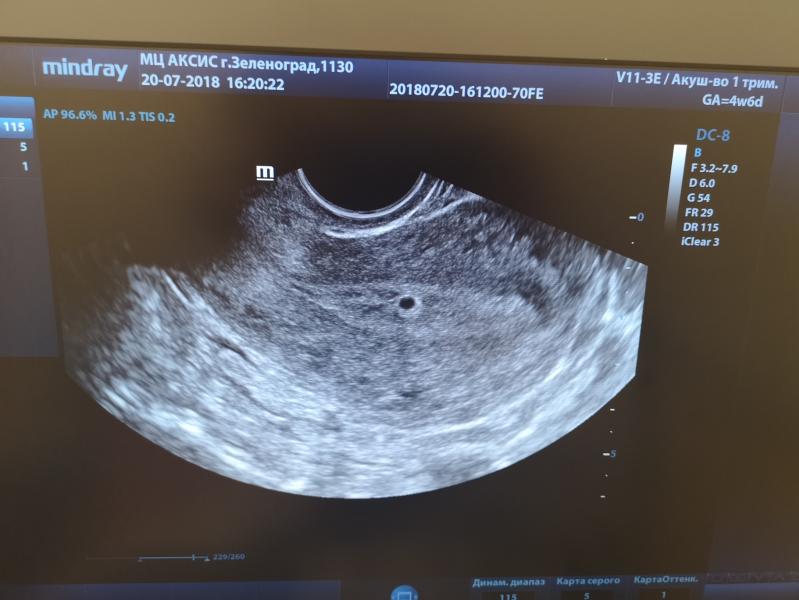

Девочки, в общем только от врача. Срок 4 недели и 6 дней, хгч в норме (626),прогестерон маловат (25,2). Назначения: витамины Фемибион, Йодомарин 100 мг, дюфастон и Магне B6. Посмотрела на УЗИ и тадаааам! Плодное яйцо в маке, чёткое такое. Внутри конечно ещё ничего не видно, но это на меня произвело такое впечатление, слезы брызнули из глаз, не спрашивая разрешения))) сколько уже было беременностей, все срывалось на небольшом сроке и никогда не видно было ничего на УЗИ. Один раз правда разглядели яйцо в трубе, упрятали с внематочной, но не подтвердилось. Так что нынешнее назначение не нервничать, витамины пить и на очередном УЗИ через 10 дней смотреть эмбрион в динамике. Ура? УРАААА😍😍😍